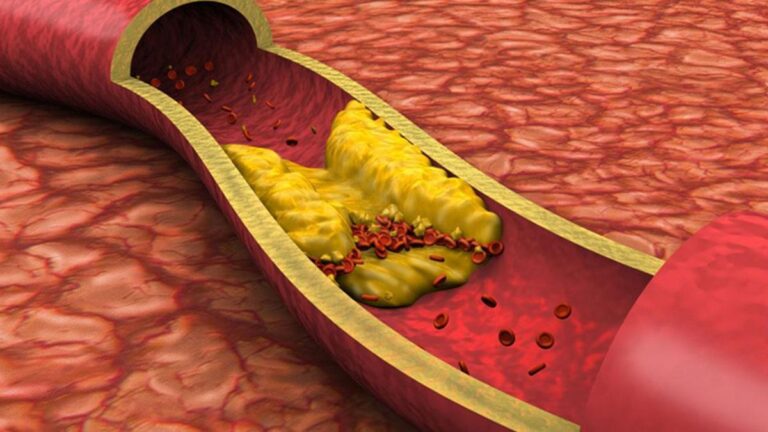

Kolesterol nedir? Kolesterol belirtileri nelerdir?